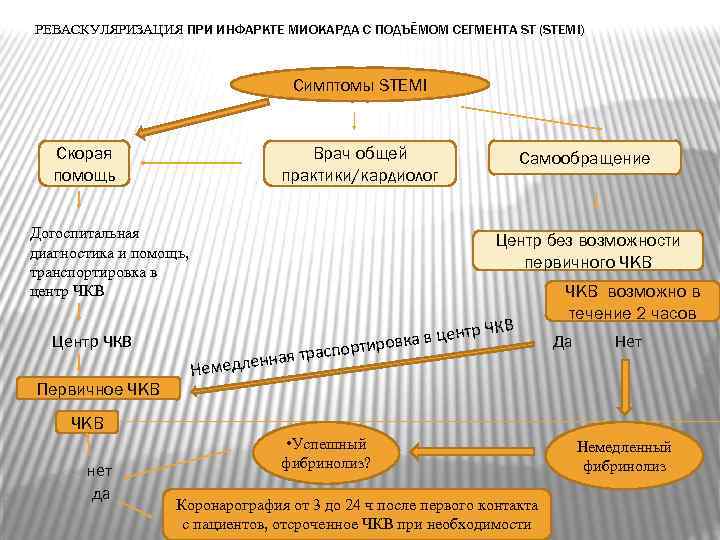

РЕВАСКУЛЯРИЗАЦИЯ ПРИ ИНФАРКТЕ МИОКАРДА С ПОДЪЁМОМ СЕГМЕНТА ST (STEMI) Симптомы STEMI Скорая помощь Врач общей практики/кардиолог Догоспитальная диагностика и помощь, транспортировка в центр ЧКВ Центр ЧКВ Первичное ЧКВ Самообращение Центр без возможности первичного ЧКВ н Немедле КВ в центр Ч ровка распорти ная т ЧКВ возможно в течение 2 часов Да Нет ЧКВ нет да • Успешный фибринолиз? Коронарография от 3 до 24 ч после первого контакта с пациентов, отсроченное ЧКВ при необходимости Немедленный фибринолиз

РЕВАСКУЛЯРИЗАЦИЯ ПРИ ИНФАРКТЕ МИОКАРДА С ПОДЪЁМОМ СЕГМЕНТА ST (STEMI) Симптомы STEMI Скорая помощь Врач общей практики/кардиолог Догоспитальная диагностика и помощь, транспортировка в центр ЧКВ Центр ЧКВ Первичное ЧКВ Самообращение Центр без возможности первичного ЧКВ н Немедле КВ в центр Ч ровка распорти ная т ЧКВ возможно в течение 2 часов Да Нет ЧКВ нет да • Успешный фибринолиз? Коронарография от 3 до 24 ч после первого контакта с пациентов, отсроченное ЧКВ при необходимости Немедленный фибринолиз